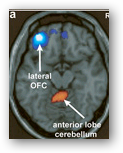

The amygdala, the brain's emotional center, and the hippocampus, which deals with memory, light up too. This helps explain a medical mystery: When epileptic seizures start in these areas, the electrical frenzy can triggers euphoric feelings called orgasmic auras.

Most patients find the experience displeasing. But in one published case, a 51-year-old woman said her auras were so pleasant she wouldn't consider antiepileptic drugs or surgery.But orgasms are more than just muscular contractions. They feel good. So how do the brains of spinal-cord-injured people sense the pleasure? "I don't know. No one knows that yet," Alexander says.